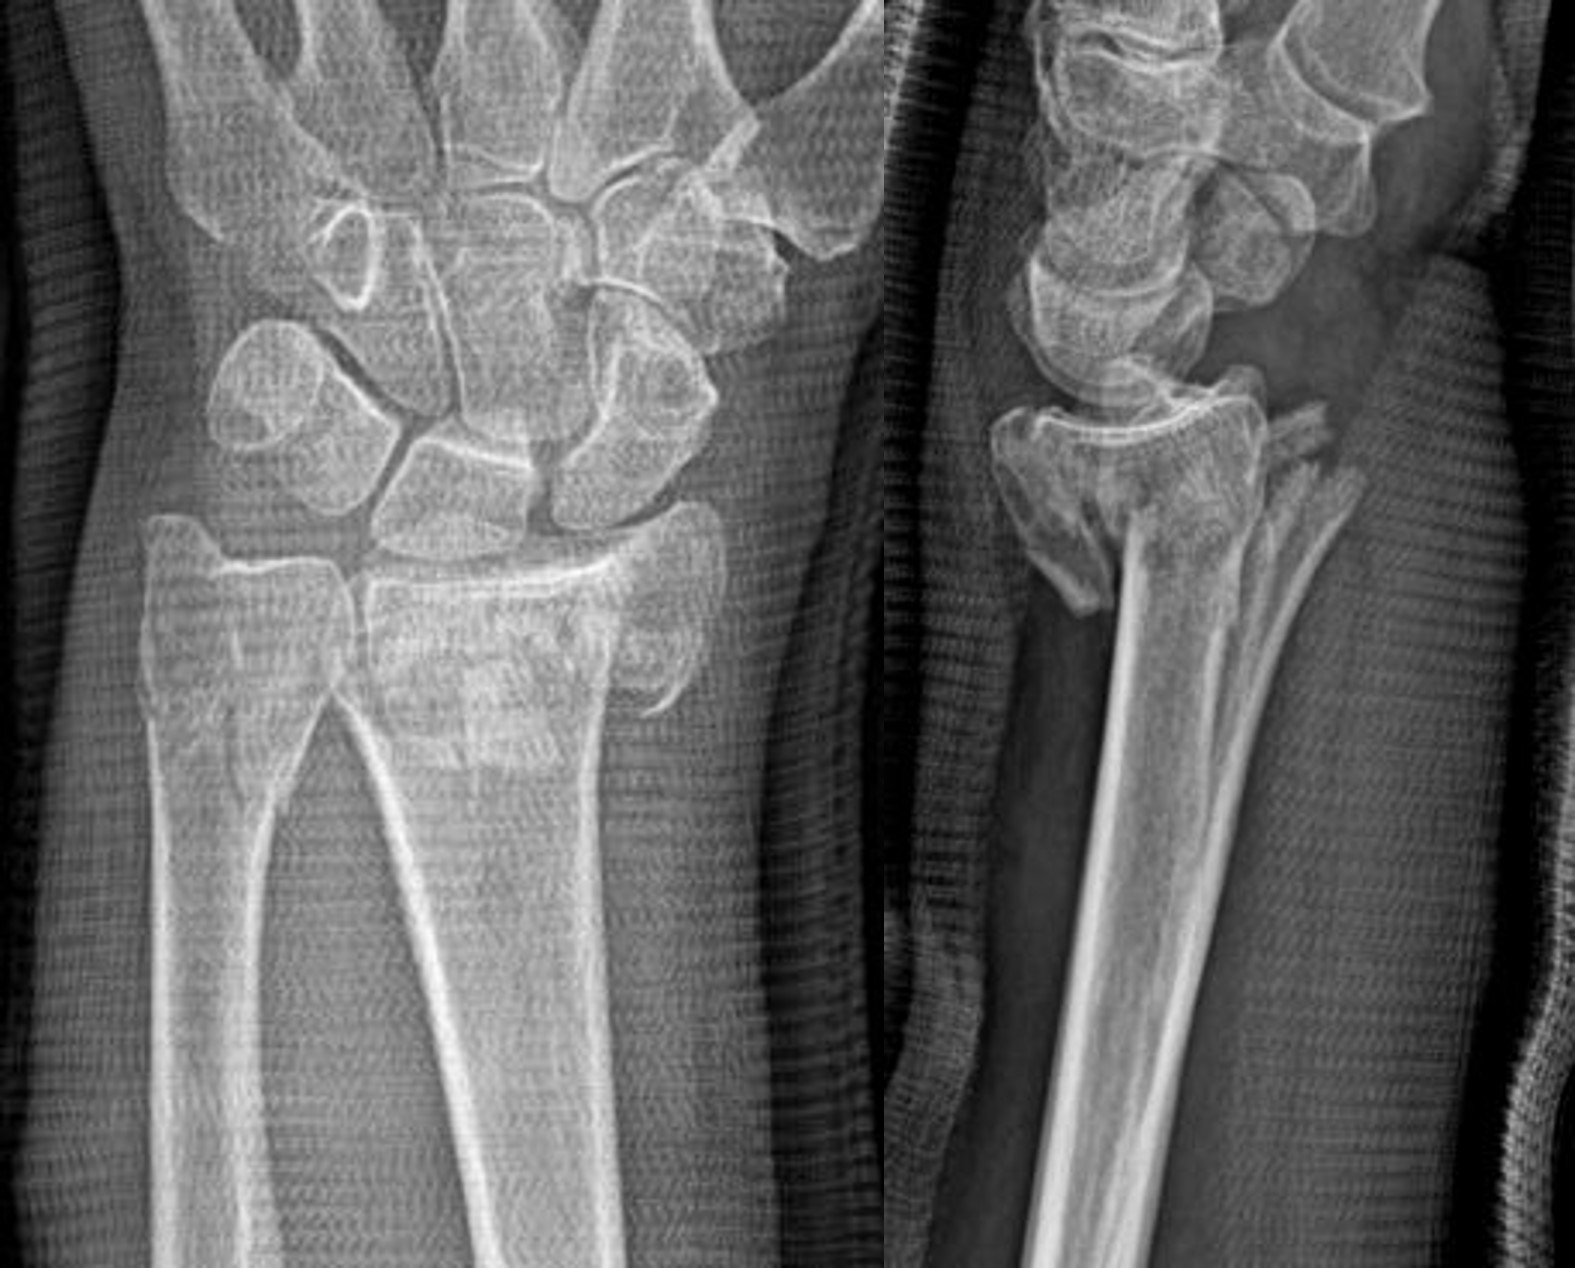

Hand Fracture

When a hand fracture occurs, our surgeons may use closed reduction (non-surgical setting of a broken bone) or fixation surgery, employing headless compression screws, to realign a fractured bone. The site of the fracture may be immobilized during the healing phase using internal fixtures such as rods or wires.